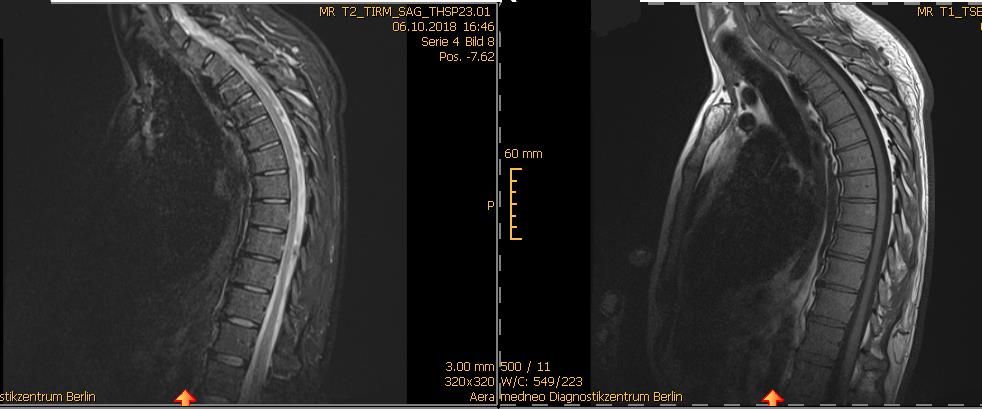

Hi alle, danke für die Aufnahme! <3 Ich wüsste gerne Eure Meinung zu meiner Hyperkyphose. Anbei ein Screenshot von der Daten-CD; und hier der Text dazu:

Indikation: Hyperkyphose der BWS.

Befund: Verstärkte Kyphosierung der BWS mit Höhenminderung der Wirbelkörper ohne Nachweis einer frischen Fraktur. Leichte Dehydrierung der Bandscheiben. Facettenarthrose. Normal weiter Spinalkanal. Regelrechter Befund des Myelons. Verstärkte Lordose im zervikothorakalen Übergang. Leichte Facettenarhrose. Kostovertebralarthrose.

eine Diagnose macht man anhand einer Röntgen(!)-Ganz-Aufnahme der Wirbelsäule von vorn und von der Seite und misst dazu die entsprechenden Winkel aus. Das MRT zeigt allerdings, dass da wohl dringend Handlungsbedarf besteht.

wenn das dein sicher im liegen aufgenommenes mrt bild ist und du neben der ws-stellung weitere probleme hast dann solltest du einen spezialisten aufsuchen, der sich mit der problematik auskennt.

die fehlstellung ist vermutlich bei einer korrekt durchgeführten röntgenuntersuchung im sitzen oder stehen noch eindrücklicher !